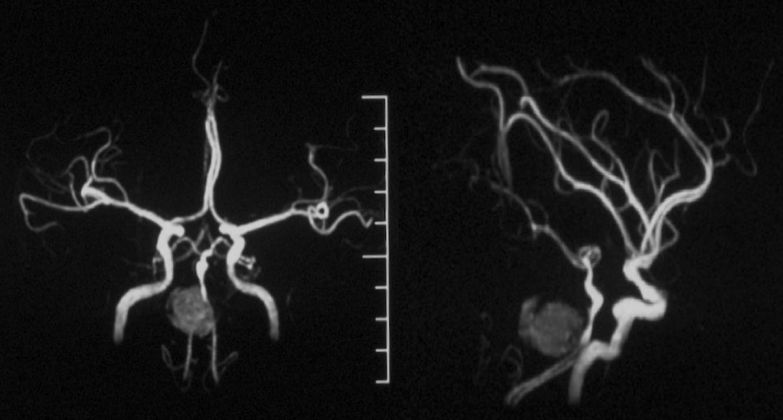

当地医院MRA:基底动脉中上段夹层动脉瘤(2019-09-16)(图5)。

图5

本院DSA:基底动脉巨大夹层动脉瘤,双侧后交通动脉未见明显开放(图6)。

图6

本院 DSA三维血管重建(2019-10-10)显示:基底动脉巨大夹层动脉瘤(图7)。

图7